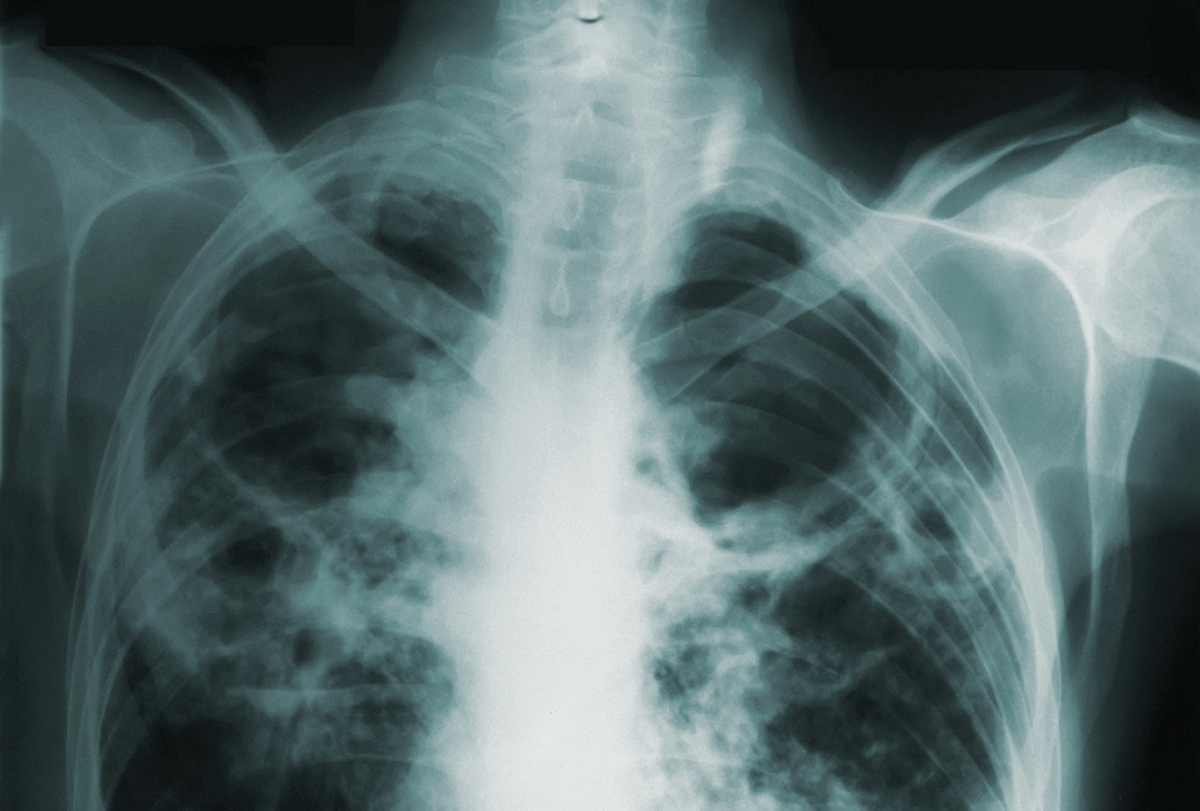

Сегодня во всем мире отмечается День борьбы с туберкулезом, призванный повысить осведомленность общественности о губительных последствиях туберкулеза для здоровья, общества и экономики и активизировать усилия по борьбе с глобальной туберкулезной эпидемией.

24 марта 1882 года д-р Роберт Кох объявил о том, что ему удалось открыть бактерию, вызывающую туберкулез, благодаря чему стала возможна разработка методов диагностики и лечения этого заболевания.

Как обстоят дела с заболеваемостью туберкулезом в Таджикистане — смотрите в нашей инфографике.